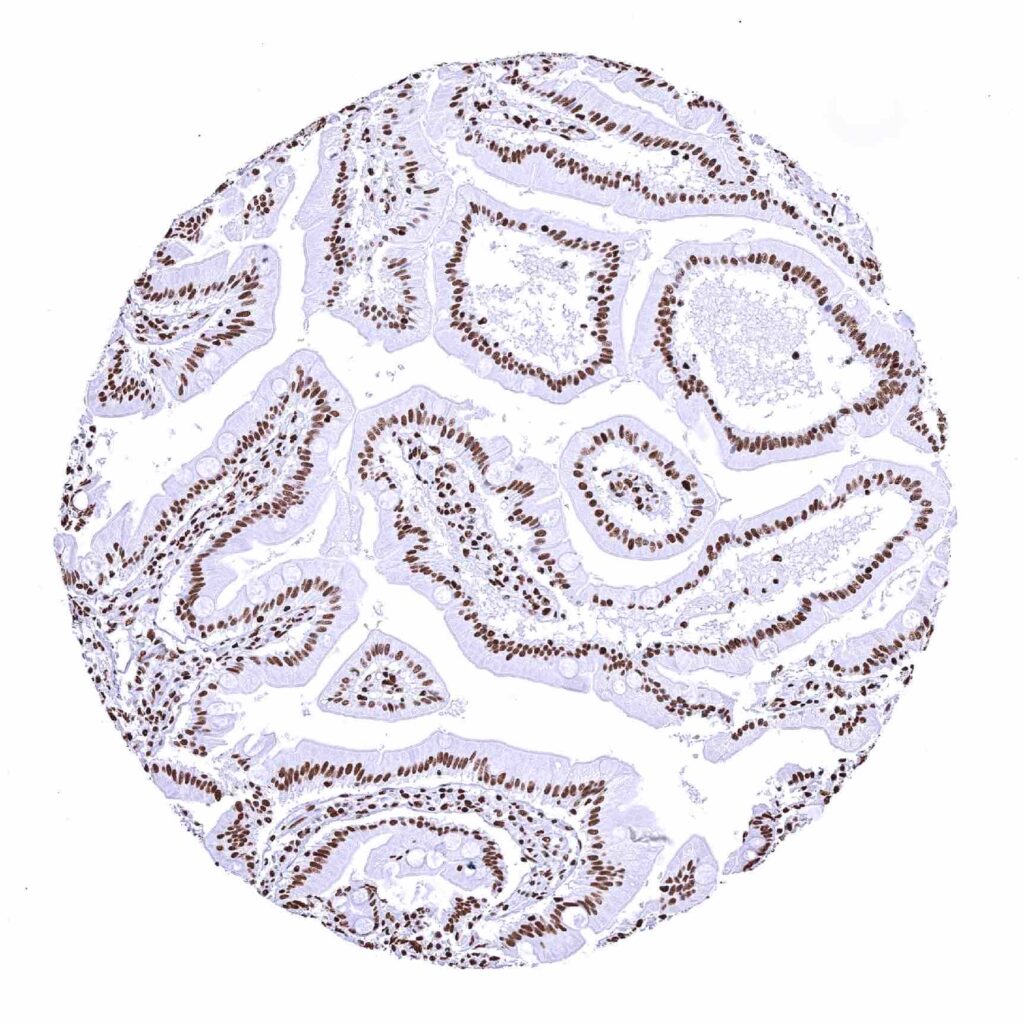

Fallopian tube, mucosa